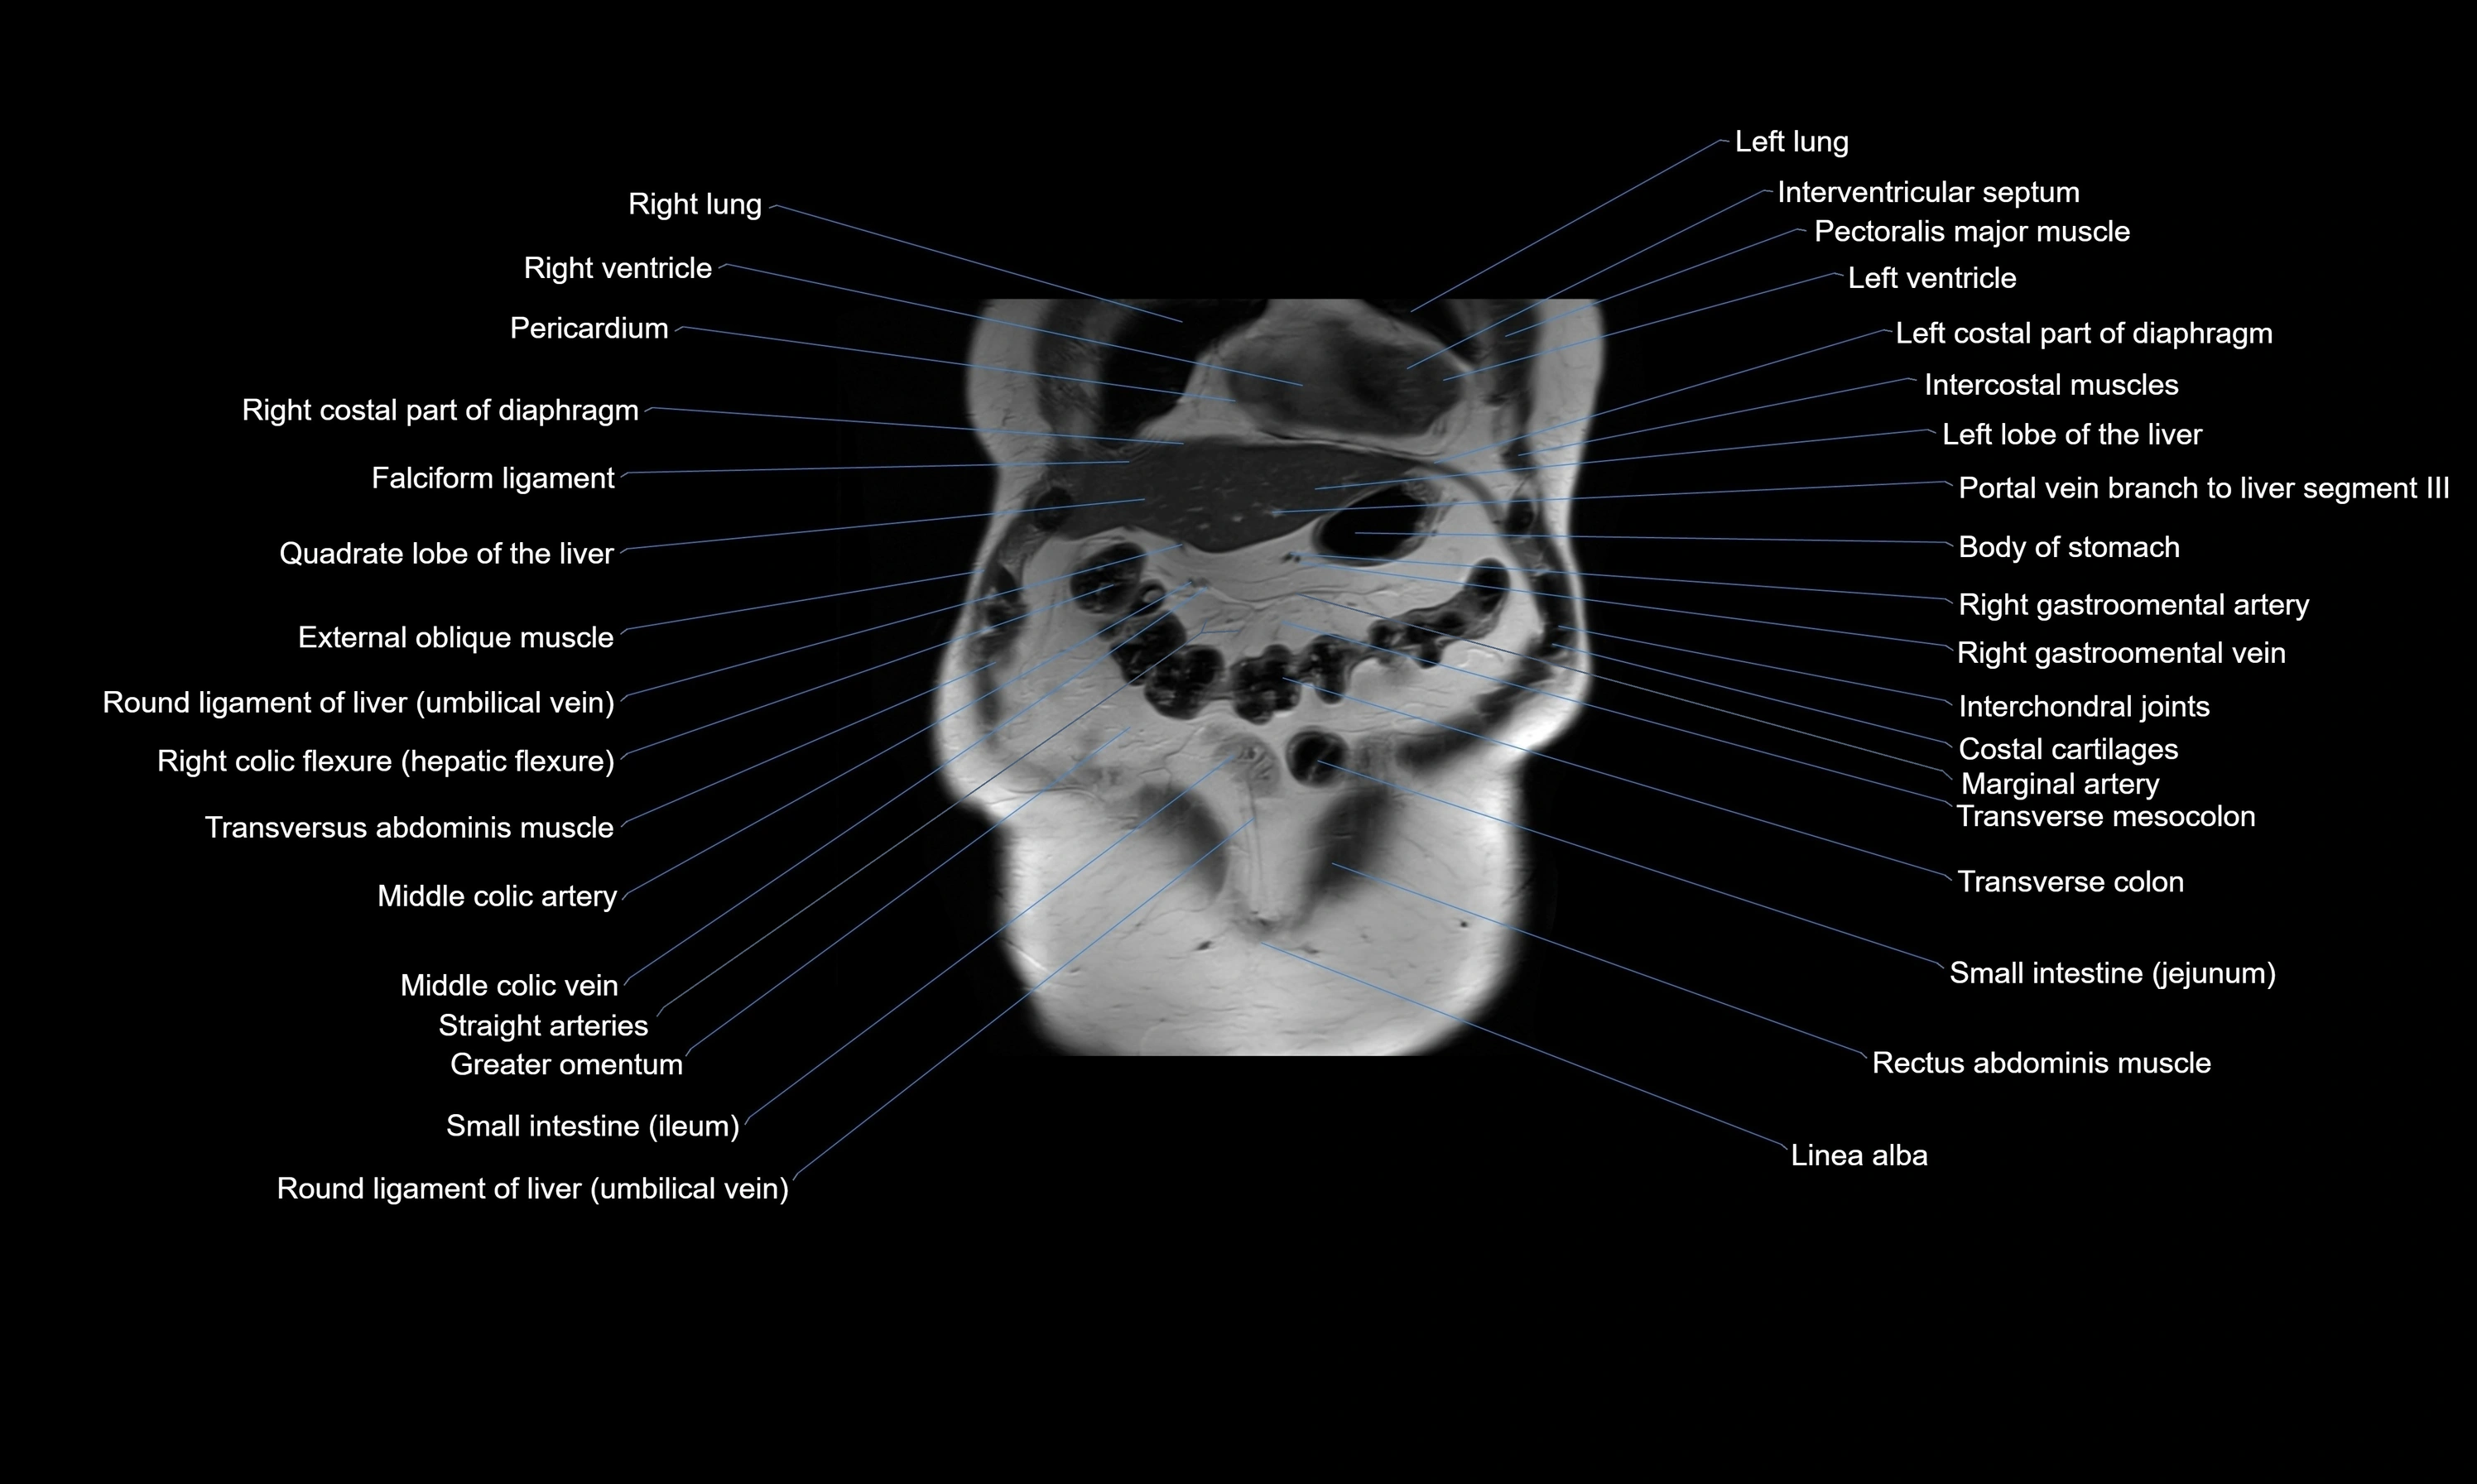

MRI images